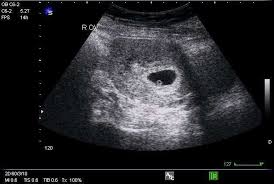

The 20-year-old quarterback stood beside his girlfriend in a private gathering with teammates and staff, smiling wider than he ever has after a touchdown. When they shared the ultrasound image — a small heartbeat, a tiny outline — the locker room erupted.